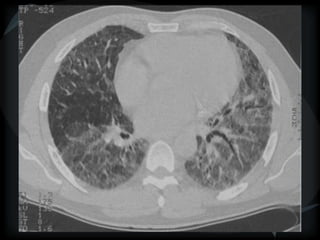

Mosaic CT Patterns

 Vascular obstruction

Airway obstruction

Vascular obstruction